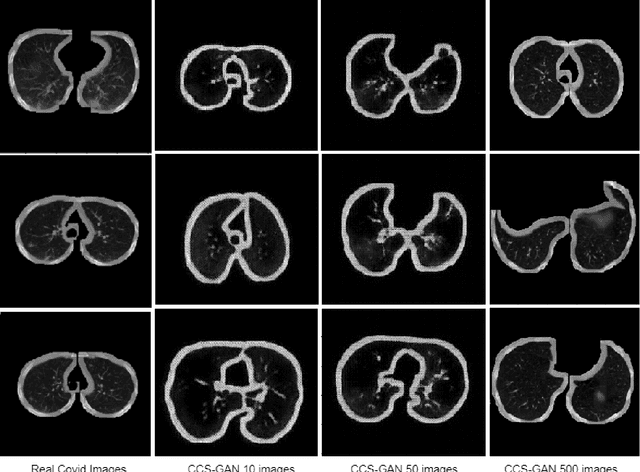

Abstract:We present a novel algorithm that is able to classify COVID-19 pneumonia from CT Scan slices using a very small sample of training images exhibiting COVID-19 pneumonia in tandem with a larger number of normal images. This algorithm is able to achieve high classification accuracy using as few as 10 positive training slices (from 10 positive cases), which to the best of our knowledge is one order of magnitude fewer than the next closest published work at the time of writing. Deep learning with extremely small positive training volumes is a very difficult problem and has been an important topic during the COVID-19 pandemic, because for quite some time it was difficult to obtain large volumes of COVID-19 positive images for training. Algorithms that can learn to screen for diseases using few examples are an important area of research. We present the Cycle Consistent Segmentation Generative Adversarial Network (CCS-GAN). CCS-GAN combines style transfer with pulmonary segmentation and relevant transfer learning from negative images in order to create a larger volume of synthetic positive images for the purposes of improving diagnostic classification performance. The performance of a VGG-19 classifier plus CCS-GAN was trained using a small sample of positive image slices ranging from at most 50 down to as few as 10 COVID-19 positive CT-scan images. CCS-GAN achieves high accuracy with few positive images and thereby greatly reduces the barrier of acquiring large training volumes in order to train a diagnostic classifier for COVID-19.